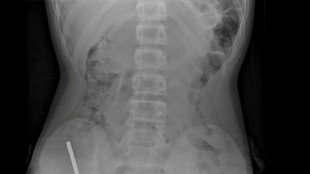

Ukraine has long struggled with tuberculosis, which was the world's biggest infectious killer before the emergence of Covid-19 and spreads in a similar manner.

Despite being diagnosable and normally easily treatable, the disease kills 1.5 million people a year globally and infects more than 10 million, according to the World Health Organization.

Ukraine records around 30,000 new cases annually and has one of the world's highest rates of drug-resistant tuberculosis, which represented 29 percent of the country's new tuberculosis patients in 2018, according to WHO figures.

But Ukraine has worked to address the problem, in recent years becoming the first country to trial a new pill against drug-resistant tuberculosis, which occurs when the two most powerful antibiotics cannot kill the TB bacteria.